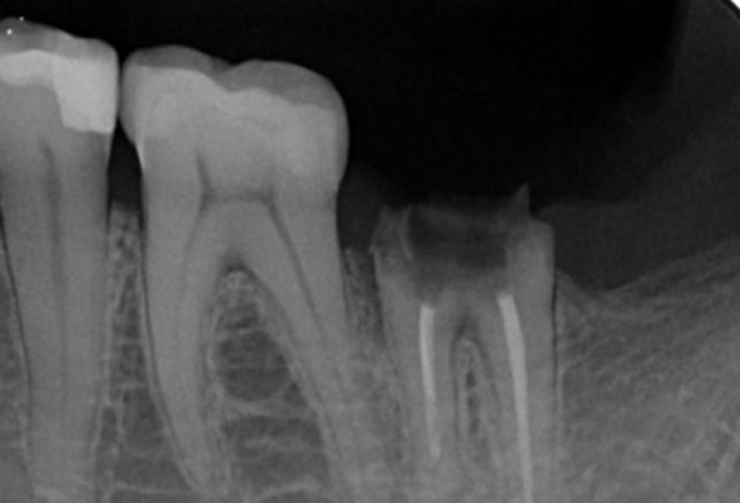

Tooth #47 underwent root canal treatment at another clinic a decade ago.

Two weeks prior to the current visit, the ceramic crown, along with its post and core, became dislodged, leaving the residual tooth structure compromised.

Pre-extraction images